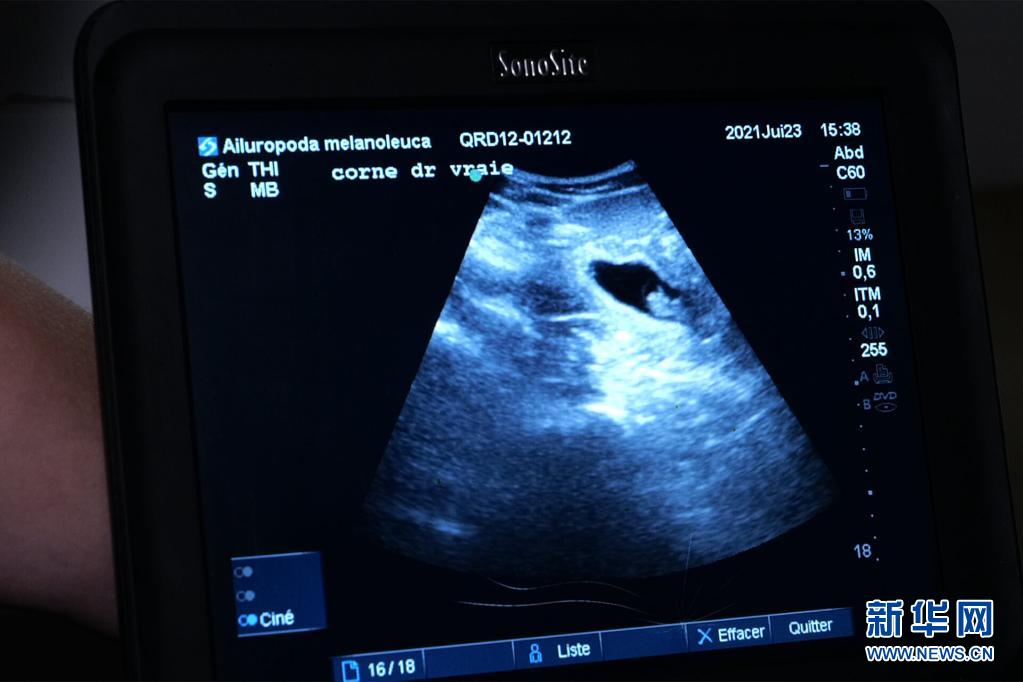

这是7月23日在法国中部圣艾尼昂市博瓦勒野生动物园拍摄的大熊猫“欢欢”的超声波检查照片。新华社发(博瓦勒野生动物园供图)

博瓦勒野生动物园当天发表新闻公报说,继20日发现“欢欢”腹中首个胚胎后,动物园兽医23日在为“欢欢”做超声波检查时,在其子宫另一侧发现第二个胚胎。

新闻公报说,双胎妊娠现象在野生大熊猫中并不罕见,发生率约为50%。